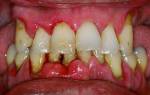

Пульпарный абсцесс

Скопление гноя в камере пульпы. После повышения в пульпе уровня серозного вещества происходит кислородная недостаточность.

Фото 1. Так выглядит осложнение пульпита, пульпарный абсцесс: на десне верхней челюсти заметно скопление гноя.

Нарушенный кислотно-щелочной баланс увеличивает количество молочной кислоты, что угнетает защитную клеточную функцию. Начинается распад тканей, и появляются симптомы абсцесса.